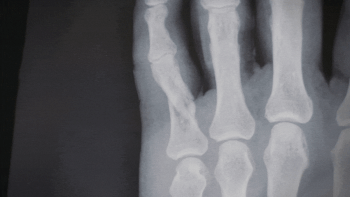

骨折の症状は多種多様でレントゲンを撮影してからでないと骨折の診断をできません。複雑骨折(解放骨折)は1秒でも早く救急車を。その他の骨折疑いも迅速対応が必要です。

「骨折」のような症状を発見した時の対応

一般的に骨折は、骨折している部分が出血や組織が傷つけられることによって腫れることが多いと言われます。

骨には骨膜という皮があり、この部分に痛覚の神経が集中しているため、骨折部が動くと痛みが生じます。

しかし、少ししかいたがっていなくても骨折していることはしばしばありますので、程度に関わらず連絡、相談、報告しましょう。

「腫脹」「疼痛」「変形」は骨折が有るものとして対応

骨折に対する応急手当とは、二次的な損傷の防止と苦痛を和らげるために、固定を行い、安静を保ちます。

患部の晴れ(患部の抹消の腫れ)、疼痛、変形の症状が見られるときは骨折している前提で大事をとって行動した方が賢明です。